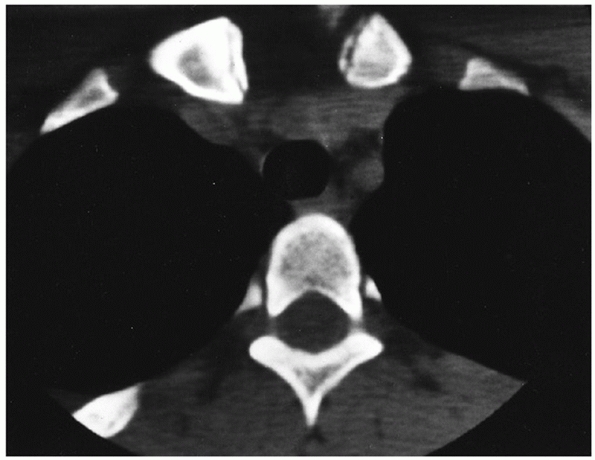

![]() |

FIGURE 40-28

CT scan of a 19-year-old patient who was involved in a motor vehicle accident and presented with complaints of chest pain and a “choking sensation” that was exacerbated by lying supine. Note the physeal injury of the medial clavicle and compression of the trachea. |